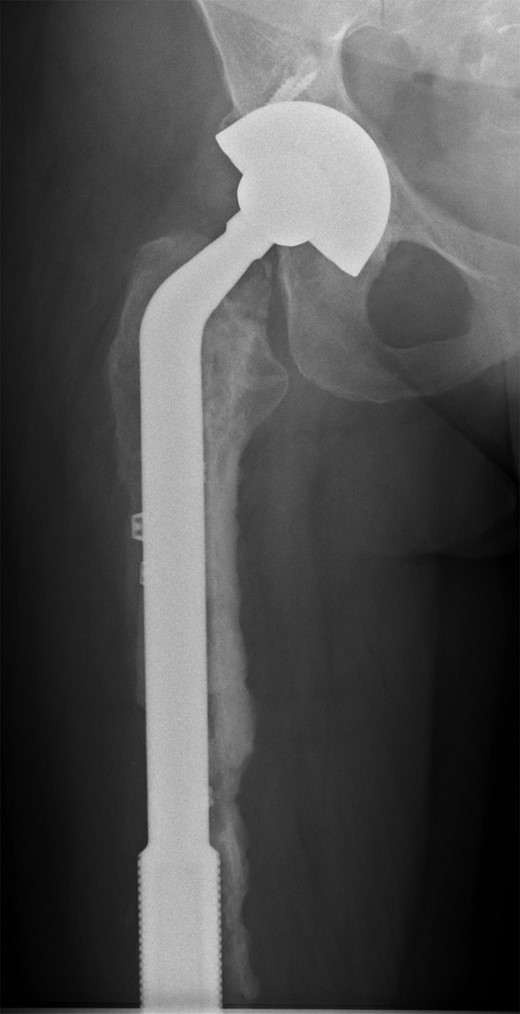

She subsequently sustained a periprosthetic fracture at the distal tip of her right total hip replacement (Fig. 1). An initial attempt was made to manage this fracture with a plate and Dall-Miles cables (Fig. 2); however, the fracture did not unite. The patient went on to have a custom-made cement-linked internal proximal femoral replacement, which had a hollow cylindrical design to accept the stem of the existing well-fixed distal femoral component (Figs 3 and 4). This linked prosthesis effectively converted her separate prostheses to a total femoral replacement, sparing her distal femoral replacement from revision. She had no problems postoperatively and recovered well from her surgery.

Periprosthetic fracture distal tip of right total hip replacement.